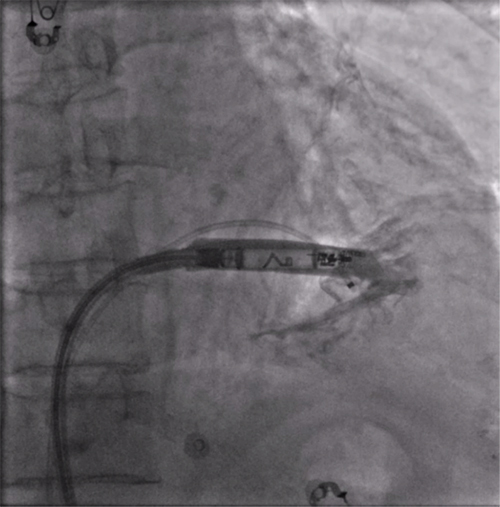

RAO造影确认位置安全

电学标测参数良好,在此旋入1.5圈后进入对接栓模式,

摇摆与电学参数测试后释放起搏器